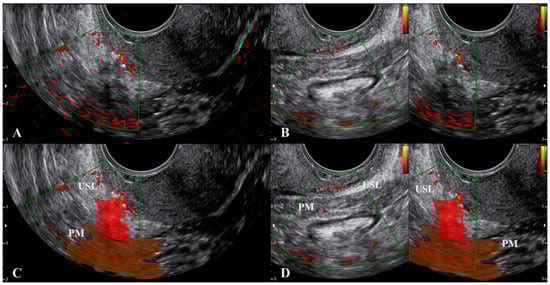

2.1. The Uterosacral Ligament

2.2. The Parametrium

2.3. The Paracervix

3. What Ultrasound Should Investigate and Detect